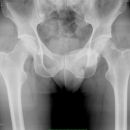

Becken / Hüfte